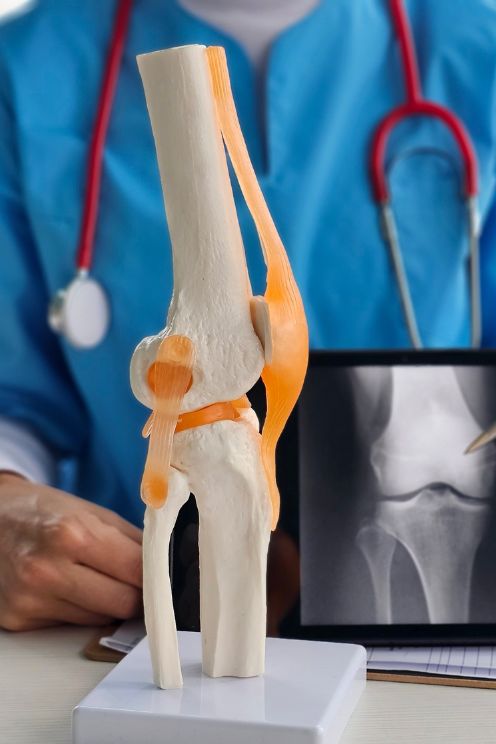

Advanced Orthopaedic Care with Modern OT Facilities by Dr S R Panda

Dr S R Panda is a reputed orthopaedic surgeon in Kolkata offering advanced facilities including General & Joint Replacement OT, Arthroscopy & Trauma OT, and Spine Surgery & Sports Injury OT, ensuring precise diagnosis, modern surgical techniques, and comprehensive bone and joint care under one roof.

Accurate Diagnosis & Personalized Treatment Plans

Accurate diagnosis with personalized treatment plans tailored to each patient’s specific bone and joint condition.